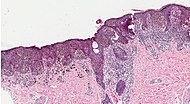

Histopathologic types[edit | edit source]

An anal melanoma

Melanoma is a type of neuroectodermal neoplasm.[76] There are four main types of melanoma:[77]

Type Features Incidence[77][notes 1] Photograph Micrograph

Superficial spreading melanoma Melanoma cells with nest formation along the dermo-epidermal junction. 70% Superficial spreading melanoma in situ on dermoscopy.jpg Histopathology of superficial spreading melanoma.jpg

Nodular melanoma Grows relatively more in depth than in width. 15% - 20% Photography of nodular melanoma.jpg Histopathology of nodular melanoma.jpg

Lentigo maligna melanoma Linear spread of atypical epidermal melanocytes as well as invasion into the dermis.[78] 5% - 10% Photograph of lentigo maligna melanoma.jpg Histopathology of lentigo maligna melanoma.jpg

Acral lentiginous melanoma Continuous proliferation of atypical melanocytes at the dermoepidermal junction.[79] 7% - 10% Photography of a large acral lentiginous melanoma.jpg Histopathology of invasive acral lentiginous melanoma.jpg